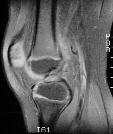

This patient is an 8 year old white male with no significant past medical

history, who slammed his knee in a car door 5 weeks prior to presentation.

He complains of right knee pain, swelling, and decreased range of motion.

The patient denies locking of the knee, but gives a questionable history

of "giving way" of the knee. On physical examination, the patient

has a small effusion. There is no medial or lateral joint line tenderness.

There is no tenderness around the collateral ligaments. Range of motion

is 30-90 degrees. There is no instability to varus or valgus stressing

at 0 degrees and 30 degrees. MacMurray test is negative. Lachman test shows

a slight increase in laxity compared to the contralateral side, but with

an endpoint. Anterior drawer test also shows a good endpoint. Posterior

drawer test is negative. KT-1000 testing was equal on both sides. The patient

was sent for physical therapy and an MRI to rule out ligament or meniscal

injury. The MRI was read by radiologist as anterior cruciate ligament tear

and small medial meniscal tear (images above).